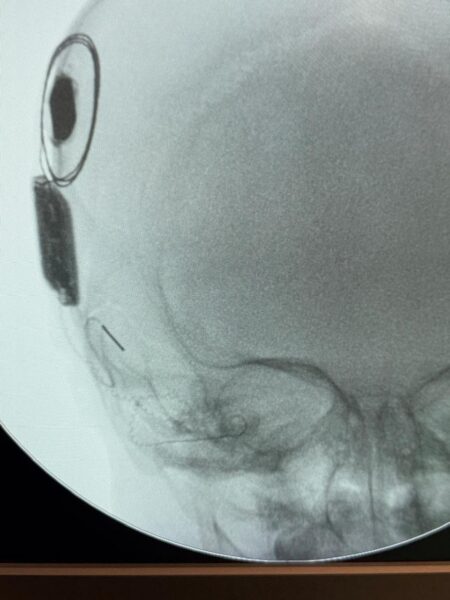

रामकृष्ण CARE हॉस्पिटल, रायपुर में पहली बार दुनिया का पहला और एकमात्र स्मार्ट, नेक्स्ट-जनरेशन Nexa Cochlear Implant 12/04/2026 को 15 महीने की एक नन्ही बच्ची पर सफलतापूर्वक किया गया।

कोक्लियर इम्प्लांट दो भागों से मिलकर बना होता है—एक आंतरिक इम्प्लांट, जिसे सर्जरी के माध्यम से कान के अंदर लगाया जाता है, और एक बाहरी साउंड प्रोसेसर, जिसे घाव ठीक होने के बाद पहना जाता है। यह बाहरी प्रोसेसर मैग्नेट के माध्यम से अंदरूनी इम्प्लांट से जुड़ा होता है।

सर्जरी के दौरान, Nexa इम्प्लांट को स्मार्ट नेविगेशन सिस्टम की मदद से कोक्लिया में स्थापित किया जाता है, जो रियल-टाइम इंट्रा-ऑपरेटिव फीडबैक प्रदान करता है। इससे इलेक्ट्रोड की सटीक प्लेसमेंट और डिवाइस की बेहतर कार्यक्षमता सुनिश्चित होती है।